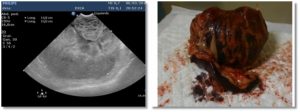

Esta es una sección realizada en colaboración de los compañeros veterinarios con los que trabaja DXIA, en la cual, compararemos imágenes reales, obtenidas durante la resolución quirúrgica, con imágenes ecográficas.

Una forma que puede ser interesante de colaboración y que nos ayuda a poder darle color a las imágenes obtenidas durante un estudio ecográfico seria comparar las imágenes reales que se obtienen durante las cirugías o intervenciones con las imágenes diagnósticas obtenidas durante el estudio ecográfico del paciente. Os quiero animar a todos a que mandéis dichas imágenes y a que este apartado crezca día a día.